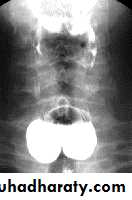

Normal Anatomy of DuodenumA.Duodenal cap.

B.Duodenal loopHypertrophic pyloric stenosisCause:A. Congenital typeB. Adult type

Epidemiology:-Pyloric stenosis is relatively common and has a male predilection (M:F ~ 4:1), and is more commonly seen in Caucasians 4.

It typically occurs between the 4-8 weeks of life. There may be a positive family history.

Incidence of hypertrophic pyloric stenosis is approximately 2-5 per 1,000 births per year in most white populations.

In a normal situation, the pyloric muscle thickness (diameter of a single muscular wall on a transverse image) should normally be less than 3 mm (most accurate 3) and the length (longitudinal measurement) should not exceed 15 mm.